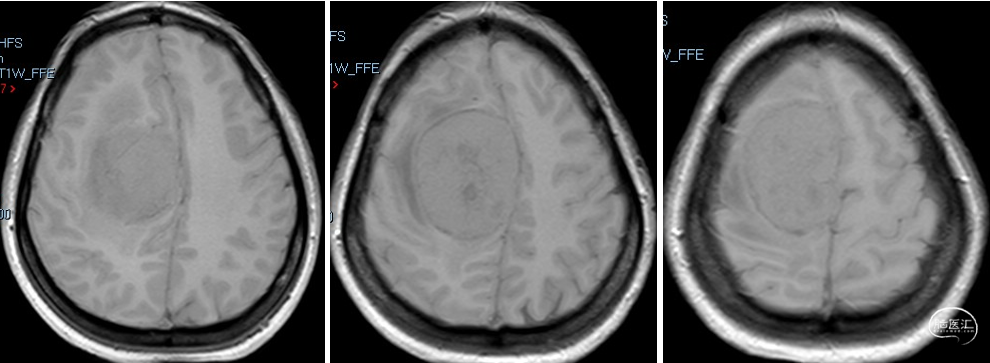

术前诊断:颅内多发脑膜瘤(右额顶部窦旁及右额部)。

术后影像